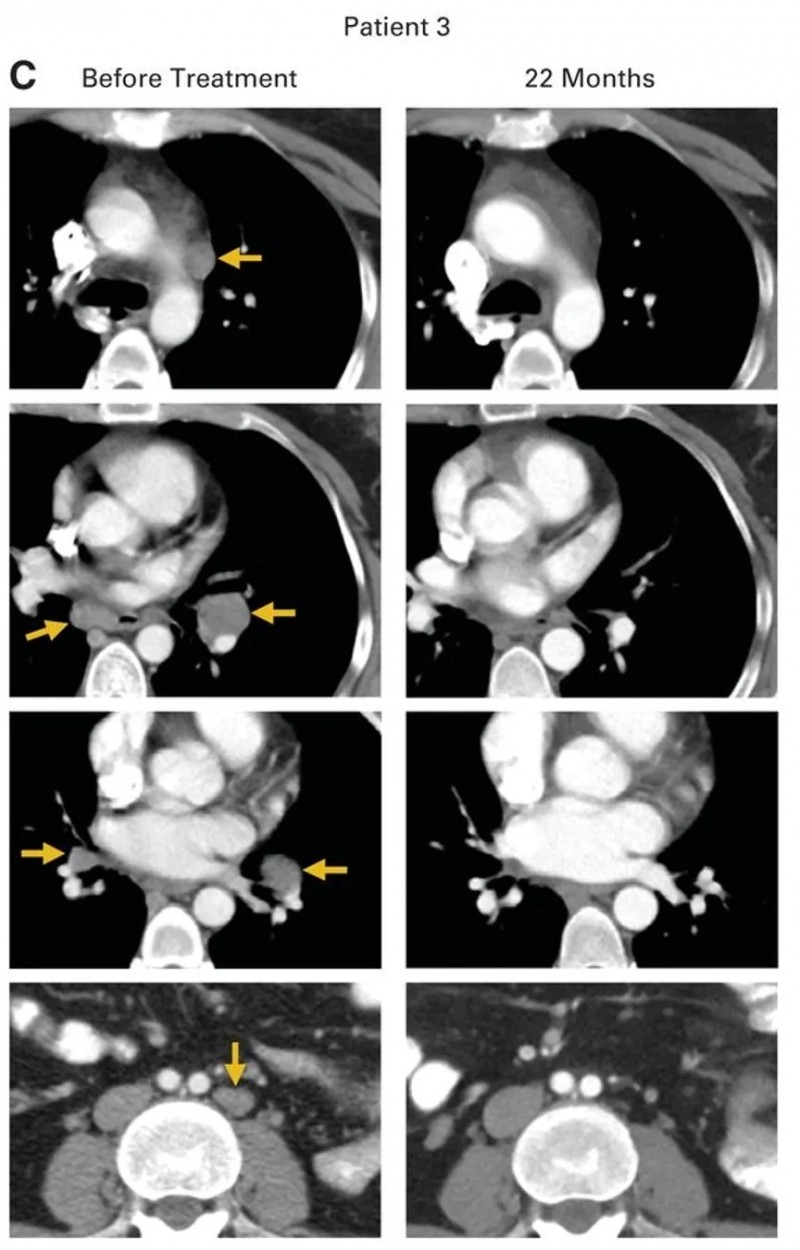

患者3为一例转移性鳞状细胞癌女性,此前接受过多线治疗:顺铂+长春新碱+博来霉素诱导化疗、吉西他滨+顺铂放化疗后,出现气管旁、隆突下及双侧肺门淋巴结转移;经拓扑替康+紫杉醇治疗后病情仍进展,治疗时肿瘤已扩散至腹主动脉旁、双侧肺门、隆突下及髂淋巴结。接受HPV-TIL治疗后,所有病灶完全消退,且治疗后22个月无疾病复发(详见下图)。

▲图源“JCO”,版权归原作者所有,如无意中侵犯了知识产权,请联系我们删除